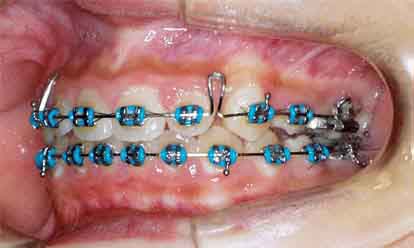

治療開始6ヶ月